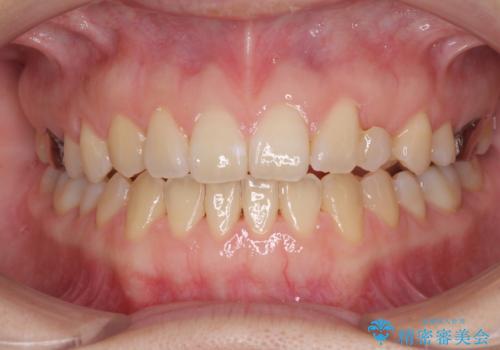

受け口で開咬を急速拡大装置とインビザラインで改善 欠損部分はインプラントにて補綴治療

- 前歯の開咬と、受け口による咬み合わせの悪さを気にして来院された患者様です。

左上は後続永久歯の欠損によりスペースがあり、矯正治療と並行してインプラントあるいはブリッジによる補綴治療が必要な状況でした。

上顎歯列が狭窄していたため、急速拡大装置により上顎骨を側方に拡大し、その後インビザラインにて矯正治療を行うこととしました。